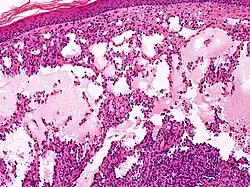

Proliferating lymphangioma, H&E stain. Sometimes endothelial cells begin to divide excessively.

Microscopically, the vesicles in lymphangioma circumscriptum are greatly dilated lymph channels that cause the papillary dermis to expand. They may be associated with acanthosis and hyperkeratosis. There are many channels in the upper dermis which often extend to the subcutis (the deeper layer of the dermis, containing mostly fat and connective tissue). The deeper vessels have large calibers with thick walls which contain smooth muscle. The lumen is filled with lymphatic fluid, but often contains red blood cells, lymphocytes, macrophages, and neutrophils. The channels are lined with flat endothelial cells. The interstitium has many lymphoid cells and shows evidence of fibroplasia (the formation of fibrous tissue). Nodules (A small mass of tissue or aggregation of cells) in cavernous lymphangioma are large, irregular channels in the reticular dermis and subcutaneous tissue that are lined by a single layer of endothelial cells. Also an incomplete layer of smooth muscle also lines the walls of these channels. The stroma consists of loose connective tissue with a lot of inflammatory cells. These tumors usually penetrate muscle. Cystic hygroma is indistinguishable from cavernous lymphangiomas on histology.[7]